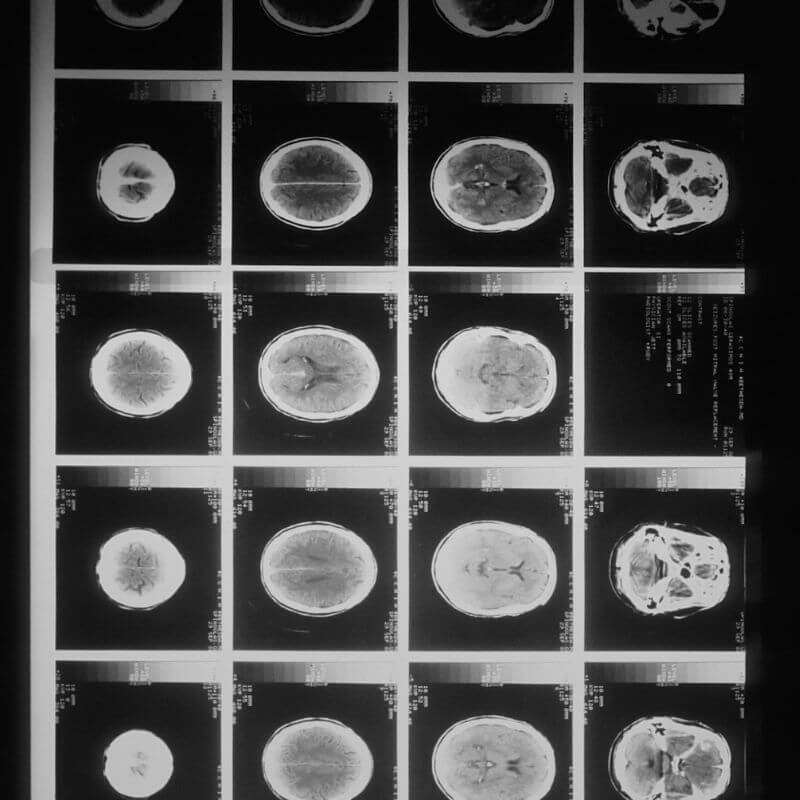

El término tomografía computarizada (TC), antes abreviado como TAC, hace referencia a un tipo de prueba para el diagnóstico por imagen que utiliza ordenadores y

El cerebro es el centro de control del ser humano. Es el órgano más complejo de nuestro cuerpo y está implicado en el desarrollo de